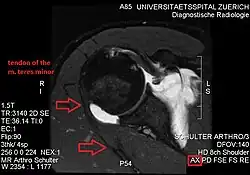

Atrophy of the teres minor muscle is often a consequence of a rotator cuff tear, but common isolated teres minor atrophies have also been found. A quadrangular space syndrome causes excessive and or chronically compression of the structures which pass through this anatomical tunnel. The axillary nerve and the posterior humeral circumflex artery pass through the space. People affected note shoulder pain and paresthesia down the arm first and foremost in abduction, extension, external rotation and overhead activity. Selective atrophy of the teres minor muscle has been seen and pulled together directly with compression of the corresponding axillary nerve branch or posterior humeral circumflex artery. Fibrous bands, cysts of the glenoid labrum, lipoma or dilated veins can occupy the quadrilateral space pathologically. Similar symptoms are common with anterior shoulder dislocation, humeral neck fracture, brachial plexus injury and thoracic outlet and inlet syndrome. It is important to include those pathologies for a complete as possible differential diagnosis.

Ultrasonography is a tool to detect a fatty degenerative atrophy of the teres minor and shows in affected muscles increased echogenicity and betimes a slight reduction in muscle bulk. MR imaging helps to consolidate the diagnosis of neurogenic muscle atrophy. Extracellular edema after traumatic events causing neural damage show an increased signal intensity on T2-weighted MRI sequences and normal intensity on T1-weighted sequences. Posterior humeral circumflex artery compression and reduced blood flow in stressful arm positions and or maneuvers can be diagnosed by a Doppler ultrasonography. The nerve should be detected adjacent to the vessel. In an elevated arm position the axillary neurovascular bundle can be seen at the posterior axillary fold just before it perforates the deltoideus, while the posterior course is well visible in the neutral position. For a detailed assessment of the artery, a MR angiography is required. The major task of an ultrasonographic examination is to rule out any space occupying mass. Additional electromyography is helpful to reveal any decelerated nerve conduction velocity, and thus denervation of the concerned muscle.[6]